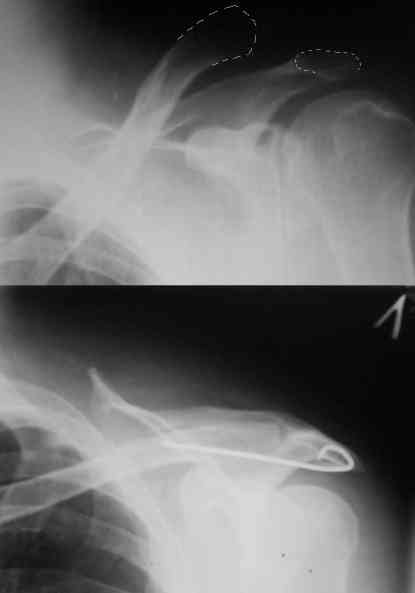

Re: Вывих акромиального конца ключицы

Внешний вид больного (травма: 09.10.2007, операция: 11.10.2007) Ориентиры доступа: овальный – пальпируемый акромиальный конец ключицы, линейный – операционный разрез

Отпрепарированы м\ткани по передней поверхности акромиона Выведен в рану акромиальный конец ключицы

Иссечение разорванного мениска

Подготовка канала в акромиальном конце ключицы сверлом 2,8 мм

Введение крючка в подготовленный канал Дистальная часть крючка подведена под акромион и фиксирована на нем путем загибания (вывих ключицы устранен)

Изготовление крючка из стержня.